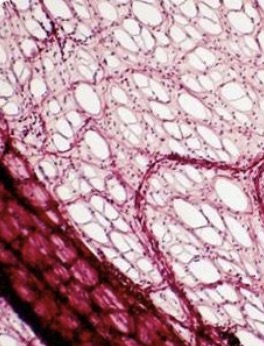

- ÿ��������206��ǣ�����λ�ɷ�Ϊ�ǡ����ɹǺ���֫�������֣�����ǰ����ͳ��Ϊ����ǡ�������̬��ͬ��һ��ɷ�Ϊ���ǡ��̹ǡ���ǺͲ���������֡�����ϵͳ��ά�������������ܵ���Ҫ��ɲ��֣���ά�����Ρ�֧�����غͱ����ڲ����١��ǵ���̬��������������ϰ�ߡ��Ͷ����ʼ��Ƿ���ijЩ����������һ���ı䡣�ڶ�ͯ����.....